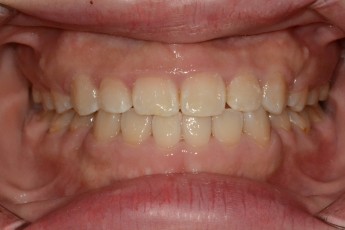

Before

After